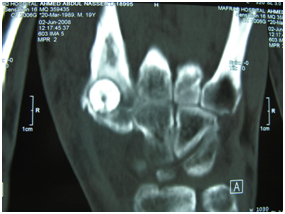

X ray (Figure 2) and CT scan (Figure 3) (Figure 4) done revealed a smooth dense cortical rounded bony lesion at the base of the second metacarpal bone with a clear even rounded edge characteristic of Bone Island. Surgical Exploration via dorsal approach, revealed erosions of the posterior cortex of the lower metaphysis of the second MC bone by the lesion (Figure 5) which was easily removed en mass (Figure 6) (Figure 7) and the cavity left (Figure 8) was filled with ipsilateral punched iliac bone graft (Figure 9).

Figure 3

Figure 4